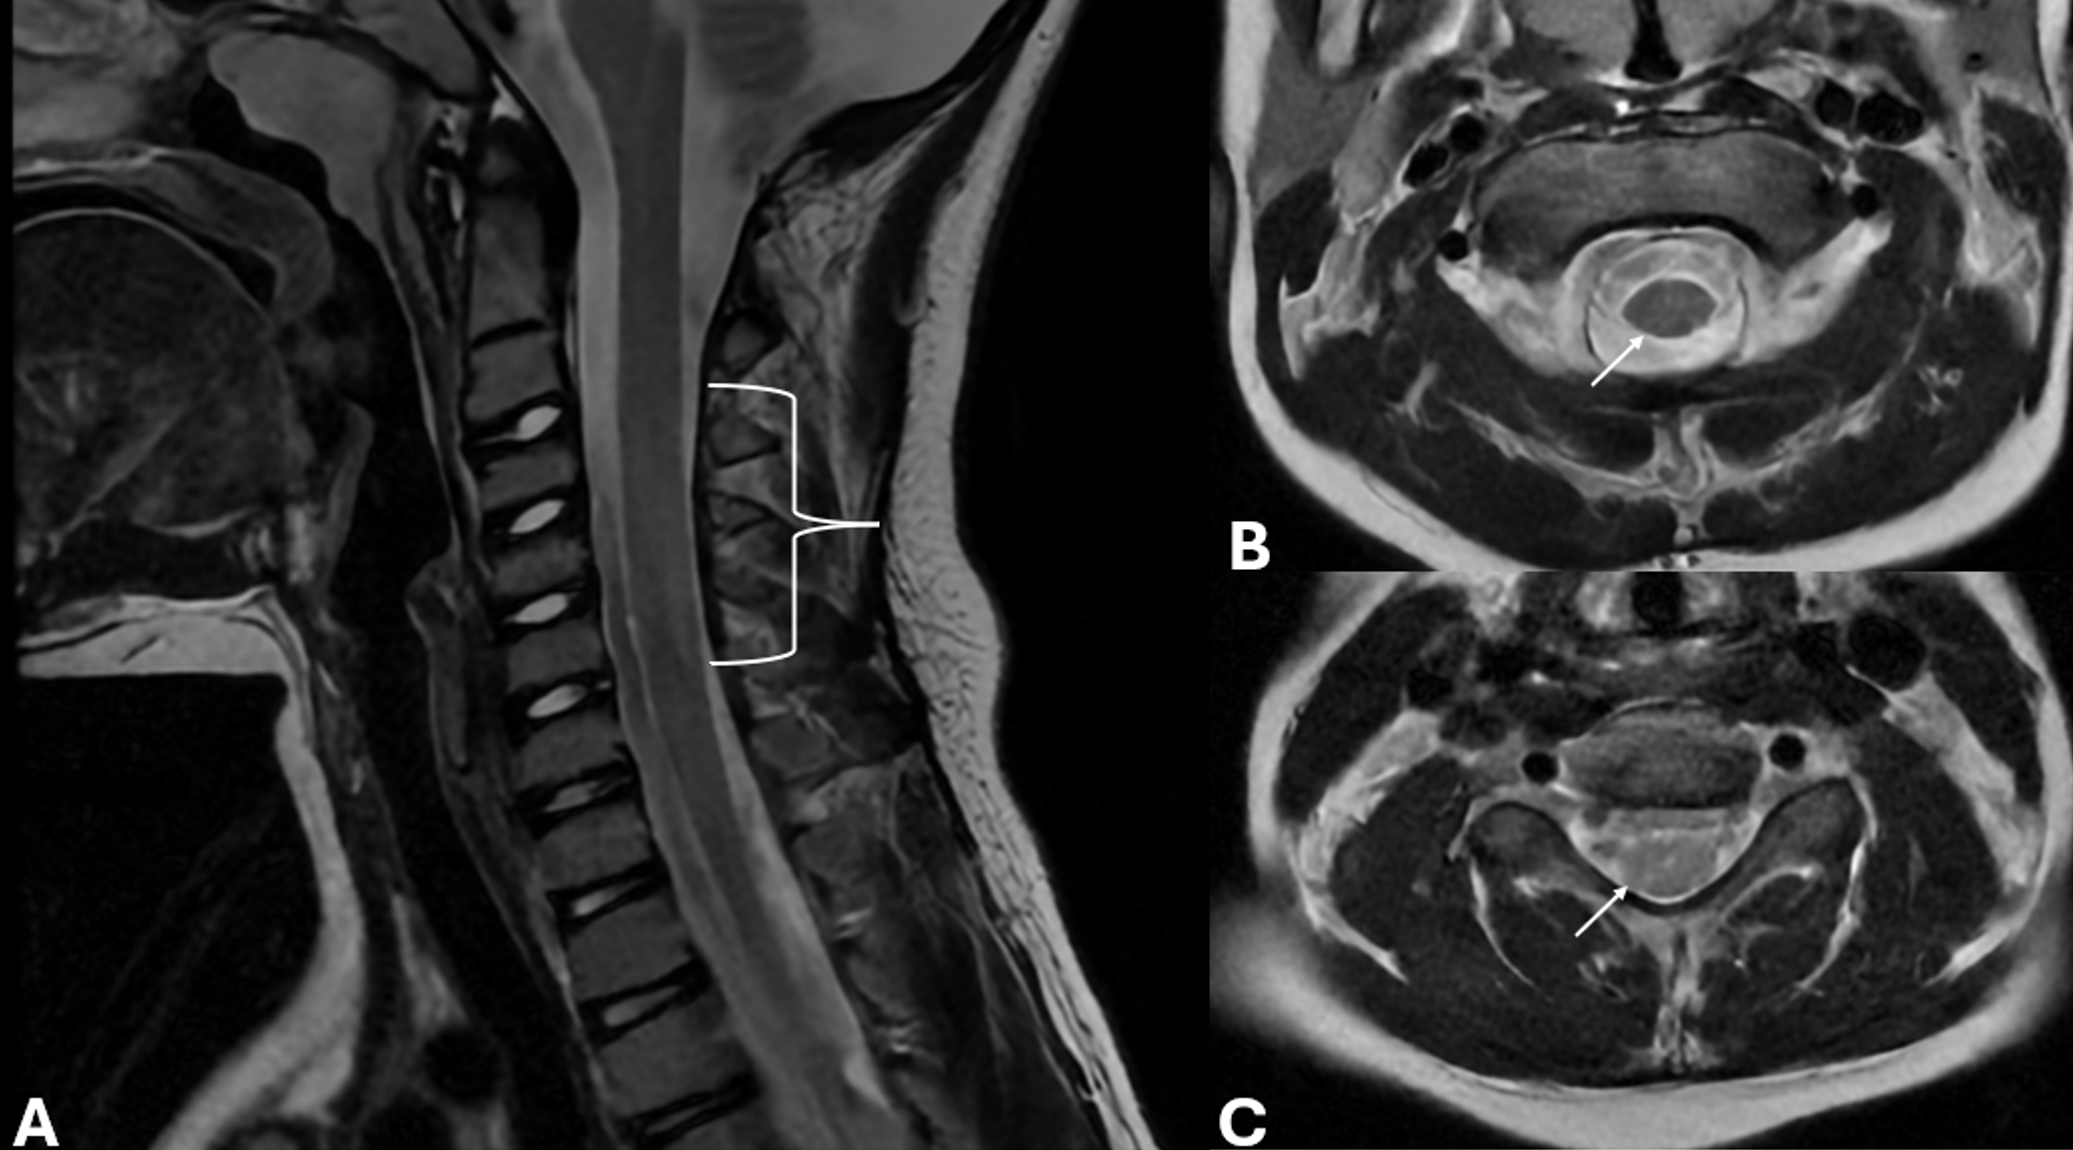

Given the severity of visual impairment and absence of other neurological signs, the patient underwent advanced imaging studies. Spinal and brain magnetic resonance imaging (MRI) was taken to differentiate demyelinating optic neuropathies (myelin oligodendrocyte glycoprotein antibody disease - MOGAD, neuromyelitis optica – NMO, and MS) in the differential diagnosis of optic neuropathy. Spinal MRI revealed diffuse intramedullary increased signal intensity in the cervical spinal cord at the C3–C6 levels on T2-weighted images; however, no associated cord edema was observed (Fig. 1). Furthermore, brain imaging demonstrated no evidence of demyelination in T2 and fluid-attenuated inversion recovery (FLAIR) sequences (Fig. 2).

During follow-up, no improvement was observed in the right eye, whereas the left eye showed a gradual decline in visual acuity over time. However, due to the variable visual performance across different visual field regions, the ophthalmologist did not report a single consistent visual acuity value for the left eye. A follow-up spinal MRI performed six months later demonstrated complete resolution of the previous lesion.